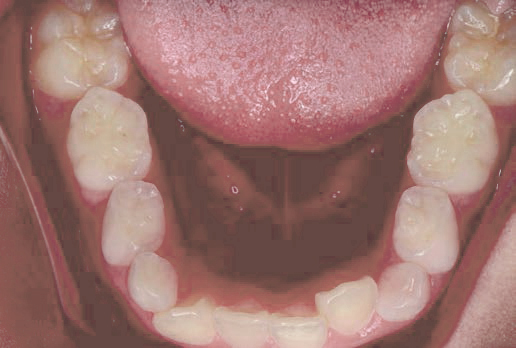

Jさん (矯正開始時:8歳)

Before

After

歯がガタガタに並んでいて、前歯の真ん中の位置が少し左にずれていました。

奥歯が生えるためのスペースが足りず、永久歯が生えて来られない状況が確認できました。

また、飲み込むとき下くちびるに力が入ってしまうクセが見られ、お顔全体の成長が遅れている様子が確認できました。

治療を終えて

歯がきれいに生えるためのスペースをしっかり確保することができ、歯並びを乱していたお口のクセも改善されたため、奥歯が生えるスペースを確保することができました。

しっかり噛めるかみ合わせを作ることが、将来の健康につながるので「よく噛む」練習も続けてもらっています。

主訴・治療内容 歯がガタガタになってきたことに悩み、無料相談に来院されました。

治療期間 3年

費用 462,000円(税込)